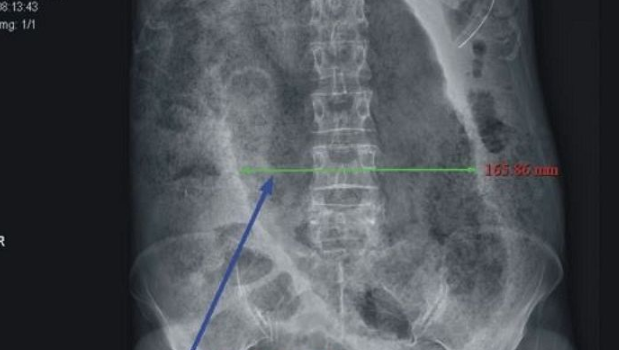

あらゆる検査をして、医師はおじいさんの大腸に大便が詰まっていることを報告しました。

そのため医師はすぐにおじいさんを手術室に運び手術を行いました。驚くことに、手術の過程でおじいさんは真っ黒に壊死してしまった腸を、なんとおおよそ30cmも除去する必要があると宣告されました。